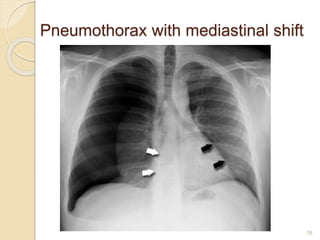

Pneumothorax with mediastinal shift